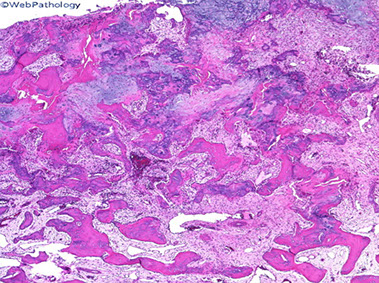

Aneurysmal bone cyst (ABC)

- usually an impressive, "benign" expansile lesion that destroys bone; etiology unknown, prolly a rxn to interosseous hemorrhage

- seen in pts <20 yo, presenting c pain, swelling, MC in metaphysis

Imaging: MC in metaphysis of long bones or posterior aspect of vertebra, "soap bubble" characteristic

- CT shows thin rim of sclerosis at margins, and can have fluid-fluid levels (double meniscus 2/2 old blood c lighter overlying watery fluid, or can have soap-bublle appearance

Micro: if intact, see cavernous blood-filled spaces lined by fibrous septae

- septae made of loose / edematous tissue c spindle cells, giant cells, capillaries and thin strands of osteoid or bone + mixed inflam

- can have lots o mits, but not that much atypia

**

Dont confuse reactive, metaplastic part c a bone forming lesion (osteosarcoma or fibrous dysplasia)

- don't miss an underlying lesion (not impossible)

- don't confuse c giant cell tumor of bone